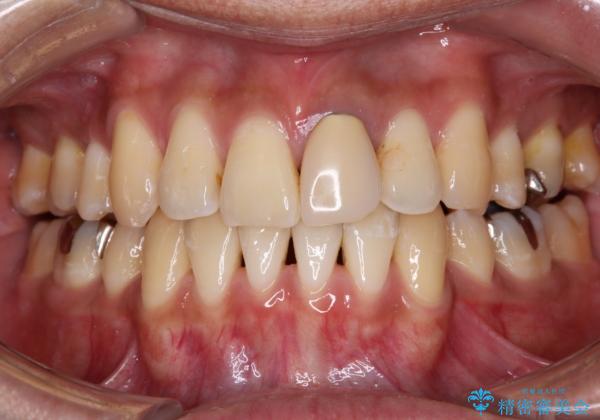

- 下顎の八重歯を気にして来院された患者様です。

左下以外、3本の第一小臼歯が既に抜去されており、左下は八重歯になっている状態でした。

左下の八重歯は手前に傾斜していたため、インビザラインによる抜歯矯正が可能と判断し、後方にある第一小臼歯を抜歯してインビザラインにて矯正治療を行うこととしました。